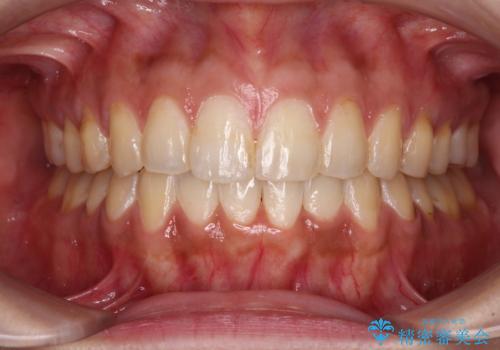

すきっ歯をインビザラインできれいな歯並びに改善

- 前歯の隙間を気にして来院された患者様です。

隙間や叢生の程度はそれほど著しいものではなかったので、インビザラインでもワイヤー矯正でも対応可能でしたが、極力目立たない装置を希望されたため、インビザラインにて矯正治療を行うこととしました。

すきっ歯の原因は色々ありますが、嚥下や発音時の舌突出癖が大きな原因となることがあります。

こちらの患者様も強い突出癖があったため、舌のトレーニング指導を行いました。